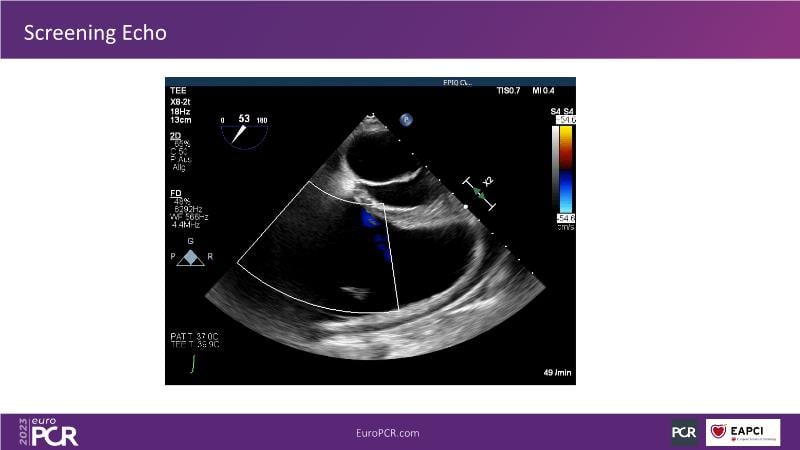

Discover the comprehensive guide to heterotopic valve replacement for patients experiencing right heart failure and tricuspid regurgitation. Join this session to gain insights into patient selection criteria, delve into the concept behind this innovative procedure, and grasp the fundamental aspects of its execution.